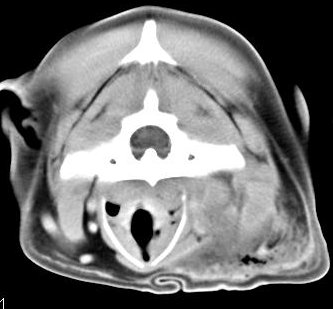

imágenes de TC en el perro | ||||||||||

ejemplo de imágenes de TC en el perro. Nótese la celulitis en la región parotídea izquierda | ||||||||||